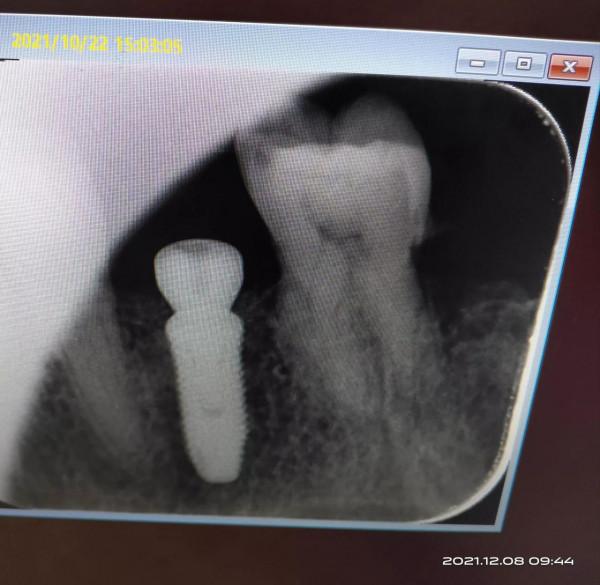

手術中痛苦不大,術後腮部有點腫,到了晚上傷口有點疼但能承受,服了三天消炎藥,含漱了七天的氯已定漱口水,一週後一切正常。下圖是植入的種植體

圖中可以看出植入體和牙骨結合以上是我的種植牙的過程和體會希望能對種植牙抱有困惑的人有所幫助。